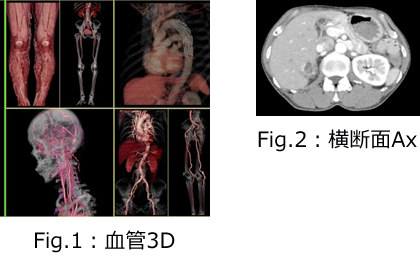

放射線部門が担当するのは、①X線撮影(レントゲン)・X線透視 ②CT撮影 ③超音波検査です。